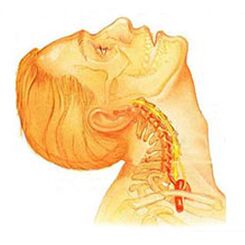

Osteochondrosis is one of the most common diseases of the musculoskeletal system, which manifests itself as a result of certain dystrophic changes in the vertebral cartilage, during this pathological process, the spinal disc is often affected. Its structure, which is an intervertebral cartilage disc, provides flexibility, and also allows the human spine to move, that is, it provides movement.

With osteochondrosis, a number of processes occur that cause degeneration of the vertebral discs, as a result of which they begin to lose elasticity and reduce the level of flexibility, and during this time the disc itself becomes quite flat. The distance between the two discs is reduced, while compressing the nerve endings and blood vessels and causing severe pain. The site of nerve compression begins to swell, resulting in increased pain and greater violation.

During the development of osteochondrosis, muscle structures and most organs of the body are often involved in this pathological process. This is due to the fact that during the maximum violation of the neurovascular bundle, blood circulation and movement of muscles and organs is disrupted. For example, the most common osteochondrosis is cervical osteochondrosis, which is accompanied by pain in the back of the head, nausea, dizziness, impaired vision and often tinnitus. The disease has become "younger": a century ago, osteochondrosis was a disease of people of gerontological age, and today young people are also susceptible to it.

Osteochondrosis of the cervical spinehas local and isolated symptoms of advanced form - with a strong root dominance, that is, it contributes to the development of severe radicular pain. Symptoms of osteochondrosis of the cervical spine are accompanied by varying degrees of dysfunction, sometimes manifested in limitation of movement of the cervical spine and sudden block of function. Headaches can be exciting and paroxysmal naturally with irradiation to the interscapular area or shoulder area. In the acute period, the patient is diagnosed with an attack of pain in the neck, which prevents and restrains the movement of the head and neck. In addition to severe discomfort, pain syndrome can be accompanied by dizziness, insomnia, pain, loss of appetite, depression, eye and pharyngeal diseases.